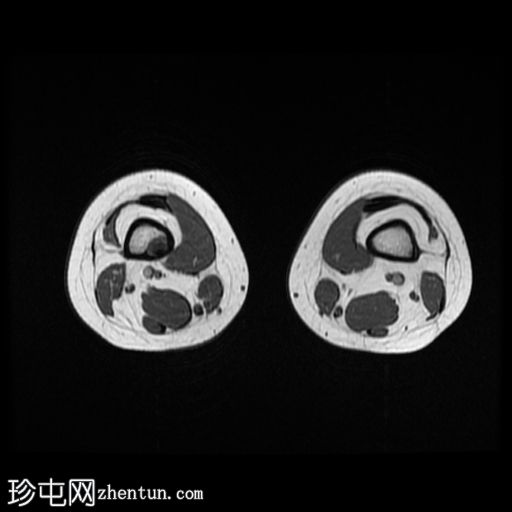

MRI

轴向

T1

股骨远端和腓骨近端干骨干部边界清晰的皮质性病变在T1加权图像上主要表现为低信号强度,在T2加权图像上表现为中等/混合信号强度,周边强化较小。胫骨结节骨髓水肿(STIR 和 T1FS/T1+C FS 可见),且无明显软组织肿胀/水肿或远端髌腱增厚/水肿,提示胫骨结节骨骺炎。